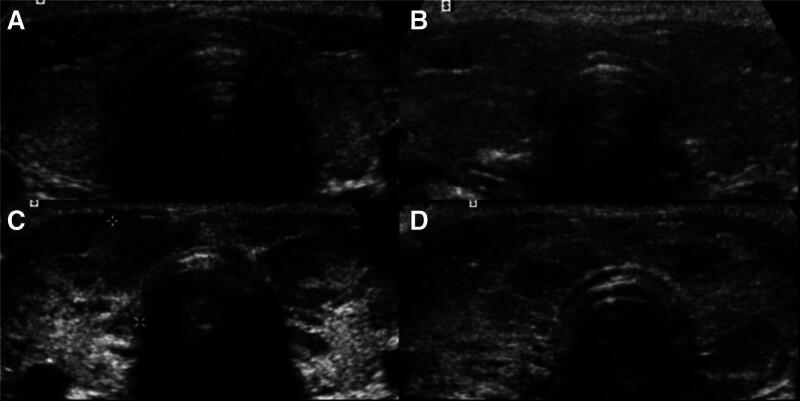

The diagnostic role of Doppler ultrasonography regarding Hashimoto thyroiditis (HT) is not fully established. We examined intraparenchymal resistive index (RI) as a Doppler parameter, thyroidal vascularity and other Gray-Scale findings in adults with HT in order to evaluate the clinical feasibility of RI in the diagnosis of this disease. The study included 48 women aged 20 to 50 years who had recently been diagnosed with HT. These participants, who were either euthyroid or sub-clinically hypothyroid during the study period, underwent sonographic examination. Thyroid glands were classified into 4 distinct patterns, using the Color Doppler Scale introduced by Schultz et al and also based on Sostre and Reyes Gray-Scale Grading System they were classified into 4 Grades. Intraparenchymal RIs were obtained in 2 locations within each lobe of the thyroid gland. Gray-Scale findings were compared to Doppler findings (RI). Also, intraparenchymal RIs were obtained in 45 healthy adults as a control group. The mean RI values were determined by calculating the mean of the RI measurements obtained from both lobes of each participant in the patient and control groups. The mean RI value was found to be 0.57 ± 0.05 (range 0.5-0.7) cm/s in patient group and 0.54 ± 0.05 (range 0.47-0.7) cm/s in control group. The results were distributed as follows: pattern 0 was observed in 22 cases, pattern I in 15 cases, pattern II in 6 cases, and pattern III in 5 cases. The mean RI values for patients with normal or nearly normal Gray-Scale findings (n = 13) and those with more pronounced Gray-Scale changes (n = 35) showed no significant difference. However, both groups exhibited higher mean RI values compared to the normal adults in the control group. The results highlight that the RI could be an effective and sensitive tool for diagnosing HT through Doppler ultrasonography.

多普勒超声检查对桥本甲状腺炎(HT)的诊断作用尚未完全明确。我们将实质内阻力指数(RI)作为多普勒参数,研究了成年HT患者的甲状腺实质内血管情况及其他灰阶表现,以评估RI在该疾病诊断中的临床可行性。该研究纳入了48名年龄在20至50岁之间、近期被诊断为HT的女性。这些参与者在研究期间甲状腺功能正常或处于亚临床甲状腺功能减退状态,均接受了超声检查。采用Schultz等人提出的彩色多普勒分级标准,甲状腺被分为4种不同模式;同时基于Sostre和Reyes灰阶分级系统,甲状腺被分为4级。在甲状腺每侧叶的两个位置获取实质内RI。将灰阶表现与多普勒检查结果(RI)进行比较。此外,选取45名健康成年人作为对照组,同样在其甲状腺每侧叶的两个位置获取实质内RI。通过计算患者组和对照组中每位参与者两侧叶RI测量值的平均值来确定平均RI值。患者组的平均RI值为0.57±0.05(范围0.5 - 0.7)cm/s,对照组为0.54±0.05(范围0.47 - 0.7)cm/s。结果分布如下:模式0有22例,模式I有15例,模式II有6例,模式III有5例。灰阶表现正常或接近正常的患者(n = 13)与灰阶变化更明显的患者(n = 35)的平均RI值无显著差异。然而,与对照组的正常成年人相比,两组的平均RI值均更高。结果表明,RI可能是通过多普勒超声诊断HT的一种有效且敏感的工具。